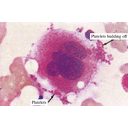

eritrocita.jpg

macrofago.jpg